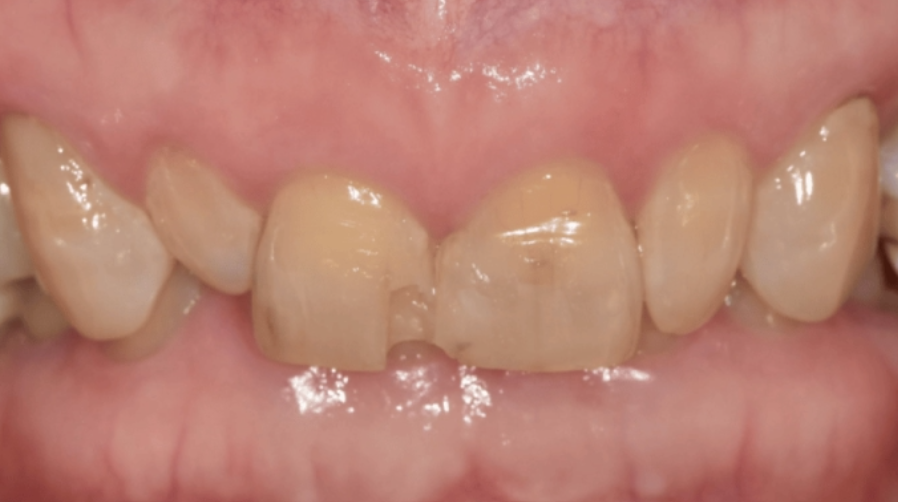

여기에 또 하나의 문제가 있었습니다.

이 분은

윗니가 아랫니를 70~80% 정도 깊게 덮고 있는

과개교합을 가지고 계셨어요.

이렇게 깊게 물리는 고합의 경우,

아래 앞니 끝이 윗니 뒤쪽과 레진에

반복적으로 부딪힐 수밖에 없어요.

그러니 레진을 다시 메워도

조금 시간이 지나면

또 깨지고 떨어질 수밖에 없었던 거였죠.